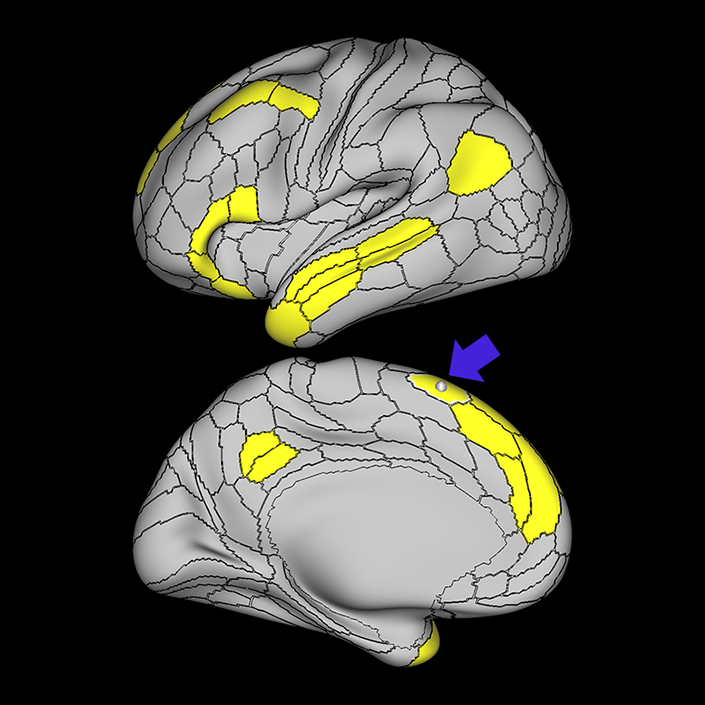

ᐅ SummaryArea STSdp (superior temporal sulcus dorsal posterior): part of the temporal lobe regions. Involved in motion processing, audiovisual integration, and facial processing. The posterior half of STSdp (as with STSvp) is strongly activated in the story-math secondary contrast, indicating a role in language comprehension. STSdp responds more strongly than STSvp to primary language tasks and to social cognition and motor tasks. ᐅ Where is it?Area STSdp (superior temporal sulcus dorsal posterior) is found on the posterior half of the lateral face of the STG and the posterior half of the superior bank of the superior temporal sulcus ᐅ What are its borders?Area STSdp borders area STSda anteriorly, STSvp inferiorly, TPOJ1 posteriorly, and A5 superiorly. ᐅ What are its functional connections?Area STSdp demonstrates functional connectivity to areas 9m, 8BL, 44 45, 47L, 47s, IFSp, SFL and 55b in the frontal lobe, areas STV, PSL, A5, and STGa in the insula opercular area, areas STSva, STSvp, STSda, and TGd, in the temporal lobe, TPOJ1 in the lateral occipital lobe, and PGi and 31pd in the parietal lobe ᐅ What are its white matter connections?Area STSdp is structurally connected to the "u" fibers of the occipito-temporal system and the arcuate/SLF. Arcuate/SLF tracts wrap around the Sylvian fissure projecting toward the frontal lobe and turn medially to terminate at 44, FOP4, IFJa, IFJp and IFSp. Local short association fibers include "u" fibers of the occipito-temrporal system that connect to STSda, STSva, STSvp, PSL and P ᐅ What is known about its function?The posterior portion of the STS is primarily involved in motion processing, audiovisual integration, and facial processing. The posterior half of STSdp (like the posterior half of STSvp) is strongly activated in the story-math secondary contrast, indicating a role in language comprehension. STSdp responds more strongly than STSvp to primary language tasks and to social cognition and motor tasks. |

A: lateral-medial

B: anterior-posterior

C: superior-inferior

DTI image |